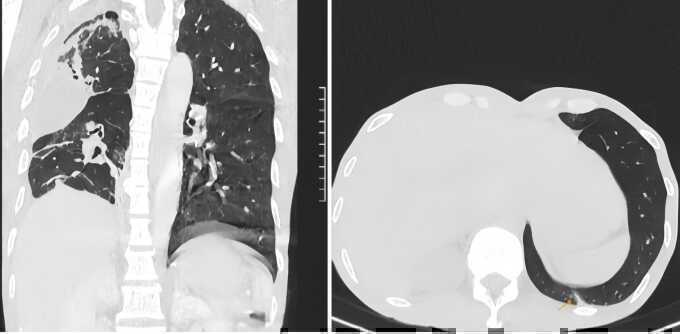

Kết quả chụp CT tại Bệnh viện Đa khoa Tâm Anh TP HCM cho thấy ổ mủ 4 cm chèn ép làm xẹp phổi bệnh nhân gây suy hô hấp cấp tính. Mủ tích tụ tạo ra ổ nhiễm khuẩn khiến người bệnh khó thở, ho ra máu.

PGS.TS.BS Vũ Hữu Vĩnh, Giám đốc Trung tâm Ngoại Lồng ngực - Mạch máu, chẩn đoán anh Tuân bị nấm phổi và lao phổi, là nguyên nhân chính dẫn đến suy hô hấp. Phổi tổn thương sẽ để lại sẹo, một bào tử nấm Aspergillus nhỏ cũng có thể ký sinh tạo hang, hình thành khối u nấm, ổ áp xe tàn phá lá phổi.

Êkíp mổ ghi nhận toàn bộ phổi phải người bệnh đã bị mủ tàn phá gây đông đặc, mùi hôi nặng từ ổ vi khuẩn kỵ khí lâu ngày. Khối u nấm xâm lấn trực tiếp vào các động mạch và mạch máu lớn, khiến chúng dính chặt vào nhau, gây khó khăn cho việc bóc tách. Sau hơn 4 giờ, êkíp hút gần một lít dịch mủ ra khỏi phổi anh Tuân, rửa sạch lồng ngực, cắt bỏ phần phổi hoại tử, bảo tồn tối đa nhu mô phổi lành và tạo hình phế quản để phục hồi lưu thông không khí.